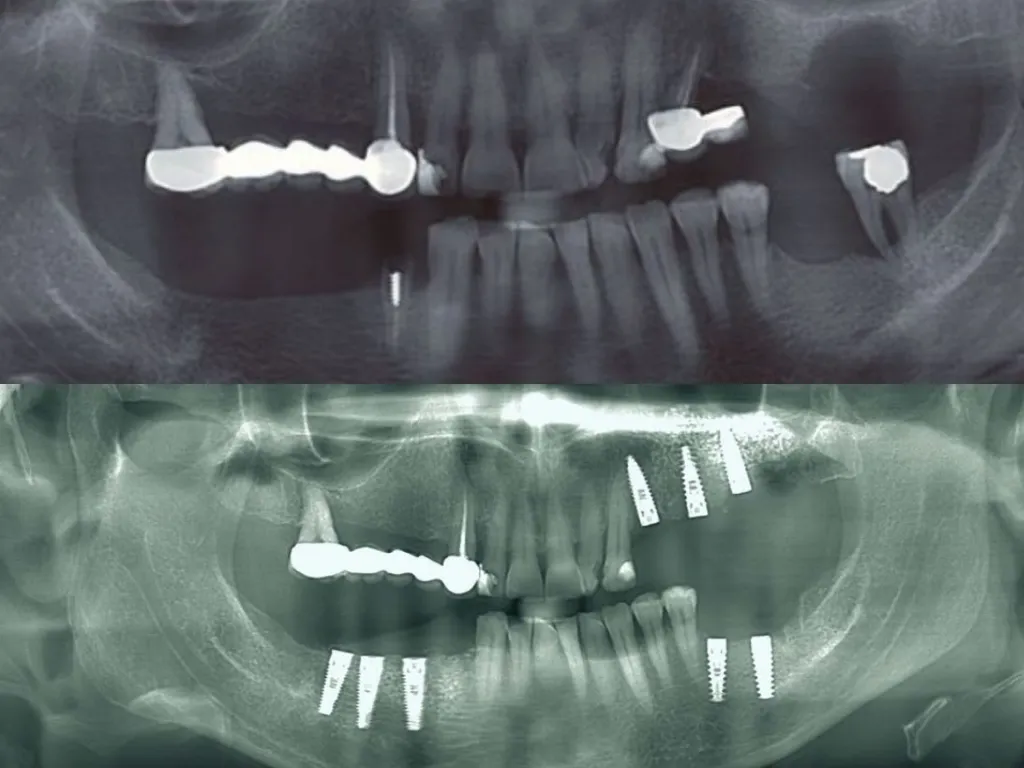

vaka_img

All-on-6 Guided Surgery

Dr. Kent Hamilton

Baştan Sona Platform Switch